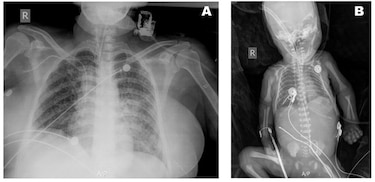

Al ingresar al hospital, su condición se deterioró rápidamente. Sufrió un paro cardiorrespiratorio que requirió maniobras de resucitación e intubación. Posteriormente, los estudios confirmaron tuberculosis miliar, una forma grave en la que la bacteria se disemina por el torrente sanguíneo hacia múltiples órganos, además de signos compatibles con meningitis.

La bebé nació mediante cesárea de emergencia con apenas un kilogramo de peso y requirió ventilación mecánica desde sus primeras horas. Días después, los análisis confirmaron meningitis tuberculosa, evidencia de transmisión vertical, es decir, contagio de madre a hija durante el embarazo o el parto. La recién nacida falleció a los 12 días. Los especialistas advirtieron que este tipo de transmisión, aunque poco frecuente, conlleva un alto riesgo de mortalidad neonatal.